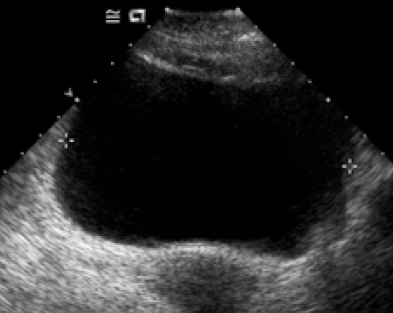

A 45-year-old man presented with mild to moderate lower urinary tract symptoms (LUTS) of one year duration with frequent history of catheterizations for urine retentions. He has no past history of infection, urethral stricture disease, or benign prostatic hypertrophy. The patient was comfortable and had no sensation of needing to void. The physical examination reveals no sensitive or motor deficits. A catheter was placed but the patient was unable to void after the catheter was removed. A postvoid residual volume obtained by noninvasive bladder ultrasonography reveals 1000 mL (figure 1). Retrograde and voiding urethro-cystography was normal (figure 2). The uroflowmetry result of the patient was Qmax: 6, 3 mL/sec. Cystoscopy reveals no obstructive lesions and a normal-appearing urethra, prostatic fossa, and bladder. Urodynamic testing demonstrated a normal capacity, compliant bladder The patient was unable to sense filling at any volume and is also unable to generate any voiding contraction (figure 3). Examination of the peripheral blood showed the red blood cell count to be 2, 2 million, WBC 28oo, hemoglobin 7.9 Gm. per 300 cc., hematocrit 28 per cent, and average cell volume 12.7 Cu. microns. In the stained blood films the erythrocytes varied greatly in size and in shape, reticulocytes were slightly less than a per cent, and the percentage of neutrophils was reduced with many of them having multilobed nuclei. Laboratory exams showed also revealed Serum antibodies to gastric parietal cells in the peripheral blood examination, the diagnosis of pernicious anemia was selected by highlighting a chronic gastritis fundic atrophy and intrinsic factor antibodies. The patient was treated by vitamin B12 orally at 500 mg / day and received a folic acid. The evolution was marked by a disappearance under treatment of urinary disturbances, macrocytosis correction and normalization of vitamin B12. At 6 months follow-up, clinical symptoms had improved, and postvoid residual (PVR) was 75 mL.